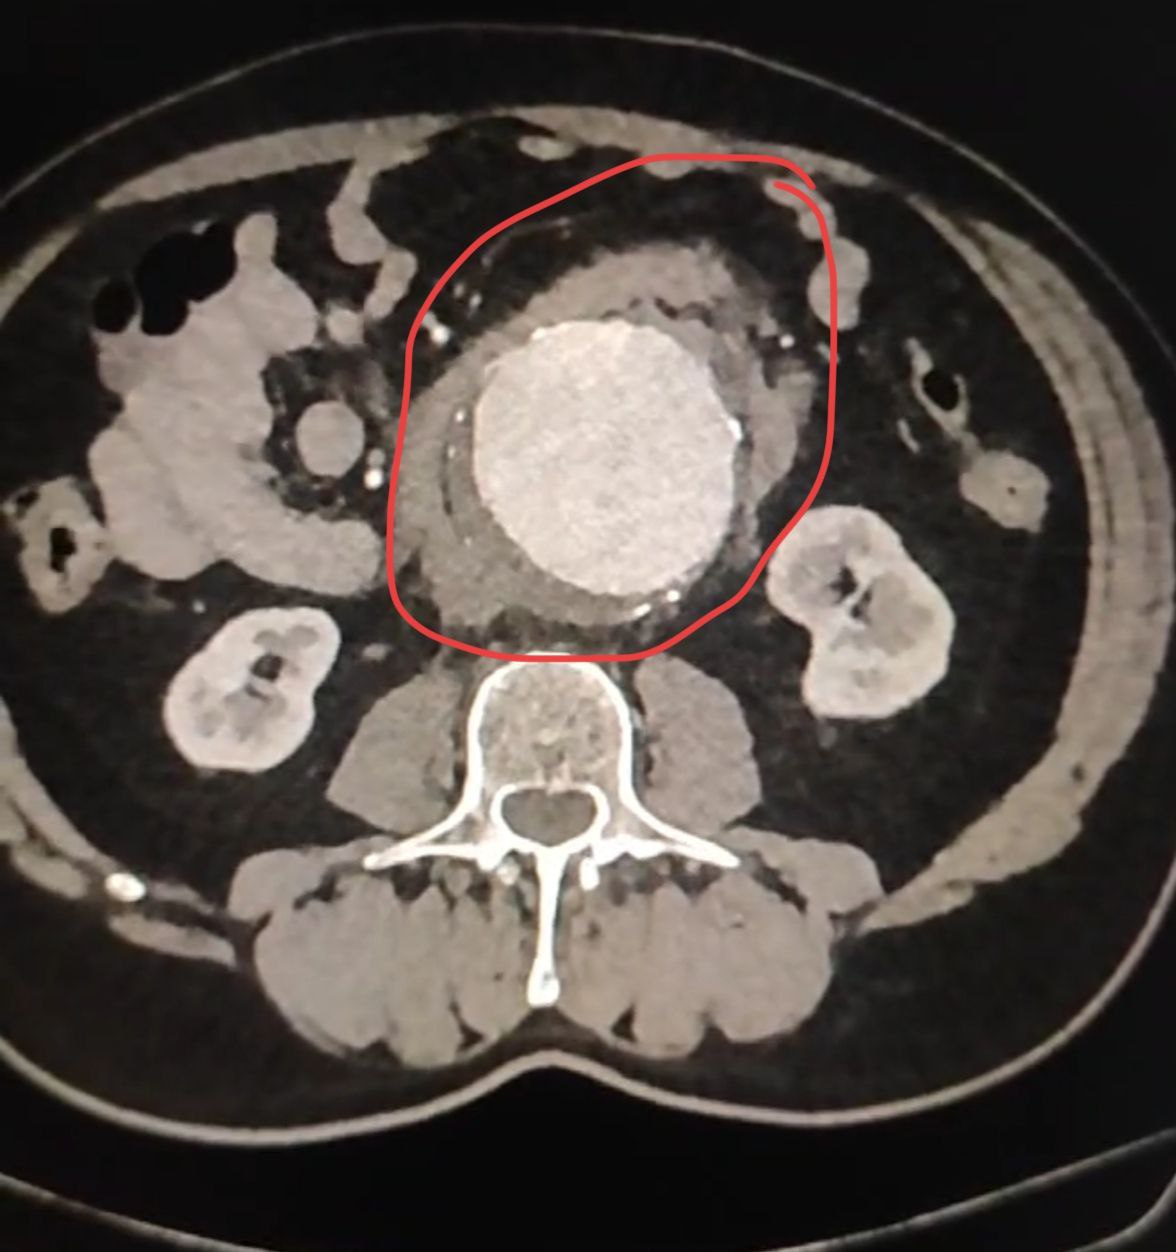

В больницу округа был доставлен 66-летний пациент с подозрением на разрыв аневризмы брюшной аорты.

Как пояснили в Долгопрудненской больнице, аневризма брюшной аорты - опасное заболевание, при котором сосуд расширяется. Аорта приобретает форму шара с истончёнными стенками, и возникает угроза её разрыва.

У больного разрыв аневризмы всё-таки произошёл, часть крови излилась в забрюшинное пространство. Летальность при данном состоянии без операции составляет 100%.

Наши врачи под руководством заведующего отделением сосудистой хирургии Алексея Варина провели экстренную операцию. Они успешно выполнили протезирование брюшной аорты: заменили поражённый участок на синтетический сосудистый протез.